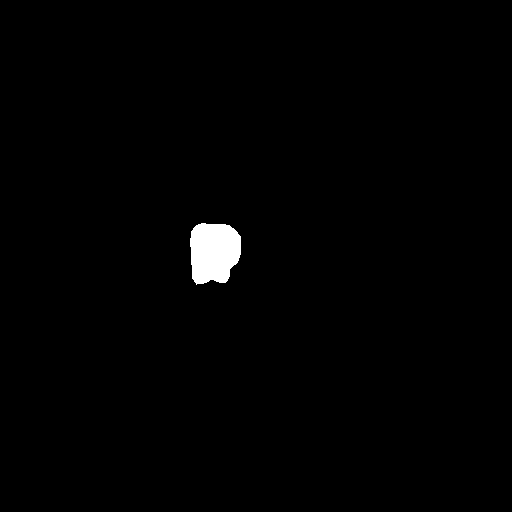

Extensive experiments have been performed in the current setup, and experimental outcomes are reported with the demonstration of numerical and statistical analyses using the proposed QFS-Net, QIS-Net [39], convolutional U-Net [18] and Residual U-Net (URes-Net) architectures [20]. The human expert segmented skull-tripped contrast enhanced DSC brain MR input image slices of size and ROIs are provided in Figure 5 as samples. The demonstration of QFS-Net segmented images followed by the essential post-processed outcome on the slice no. for class level with four distinct activation schemes () are shown in Figure 6. It is evident from the experimental data provided in Table LABEL:tab1 that the proposed QFS-Net performs optimally for the -connected quantum fuzzy pixel information heterogeneity assisted activation () with and gray scale set in comparison with other thresholding schemes and gray scale sets under the four evaluation parameters () [44]. The segmented tumors obtained using the proposed self-supervised procedure under class transition levels with four different thresholding schemes , , and are demonstrated in Figures 7- 8 for the class boundary sets and [39], respectively. The segmented images using the remaining two class boundary sets ( and ) [39] are provided in the supplementary materials section. The segmented ROIs describing the whole tumor region after the masking procedure using QIS-Net, U-Net and URes-Net are also reported in Figure 9.